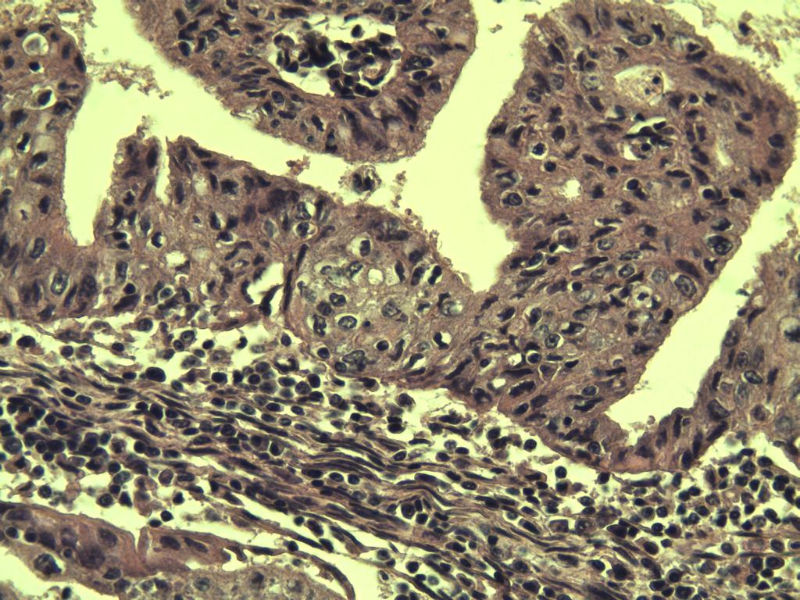

女,57岁,全切子宫一个,宫体体积 9 × 8 × 7 cm3,肌壁厚 2.5 cm,内膜菲薄,部分区域增厚达 0.4 cm(约3*2.5cm区域)。 请问各位老师  这个可以诊断子宫内膜癌了吧?      深肌层没有看到浸润。

患者因"发现下腹部包块1月多"入院  宫体体积 9 × 8 × 7 cm3,肌壁厚 2.5 cm,内膜菲薄,部分区域厚 0.4 cm(约3*2.5cm)。宫颈结构不清,长约 2.5 cm,表面欠光滑。临床诊断宫颈宫腔积液.

宫内膜样腺癌

筛状、迷路样结构

间质消失或者纤维性间质

子宫内膜样腺癌

高分化子宫内膜样癌。浸润浅肌层(深度<1/3肌层)。根据FIGO2009分期,子宫内膜癌局限于内膜层和<1/2肌层,都属于IA期。二者处理不再区别对待。